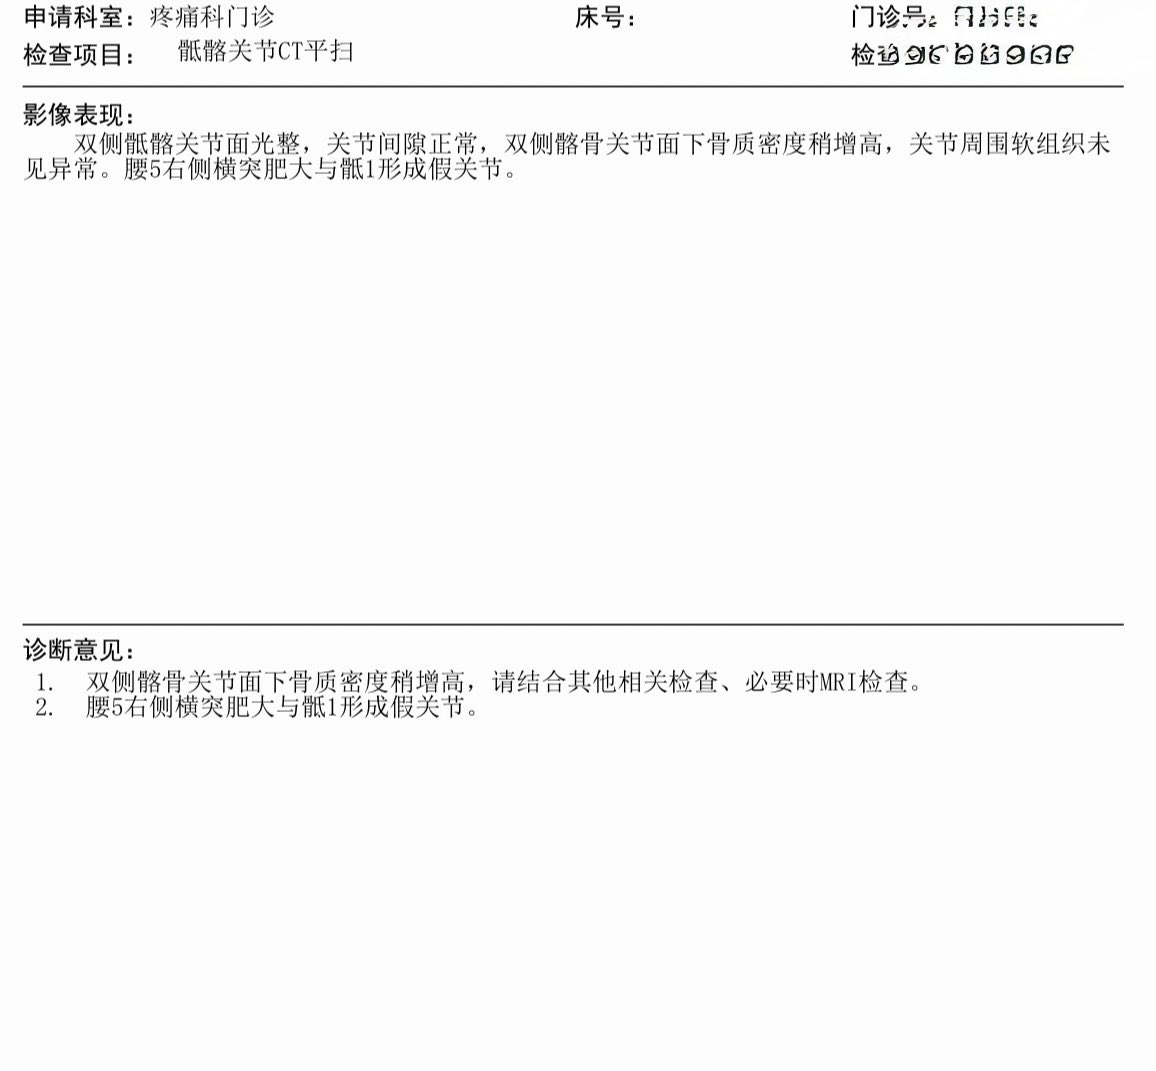

炽烈已极 @AnIncandescence@Eternal1uv9 明确是先天性发育异常,Bertolotti综合征

炽烈已极 @AnIncandescence@Eternal1uv9 假关节把额外负荷传到骶髂关节可能形成了炎症,这是继发影响。后天生活(应该和我的专业有关)导致了加重

炽烈已极 @AnIncandescence@RicardoKangAn 你在说什么。。脊柱侧弯?就算脊柱侧弯也不会让腰5右侧横突肥大与骶1形成假关节也不会让双侧髂骨关节面下骨质密度增高